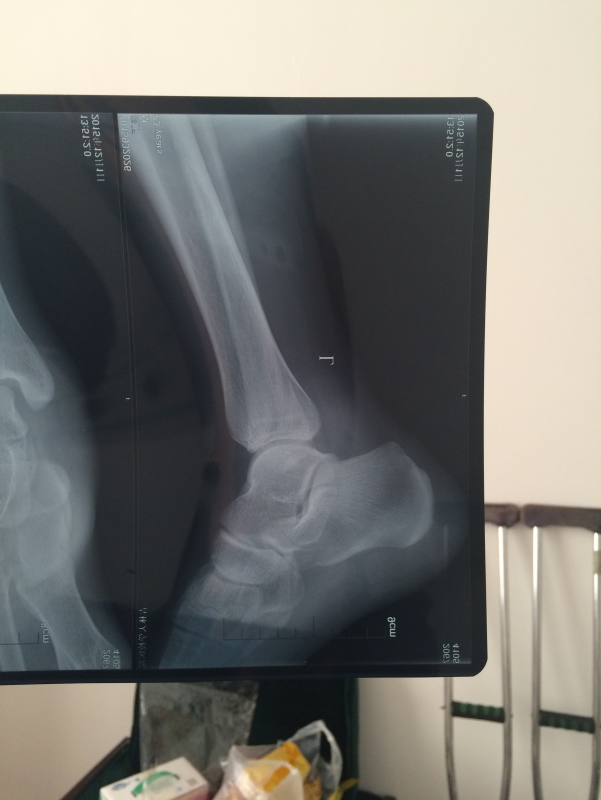

左脚踝腓骨骨折 已有10人参与

需要打钢板吗? 发自小木虫IOS客户端 |